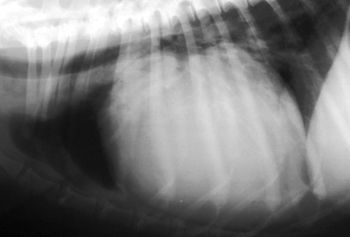

Echocardiography has emerged as the most valuable non-invasive tool for evaluation of cardiac structure, function, blood flow patterns, and has greatly diminished the need for diagnostic cardiac catheterizations and angiocardiography in many cases.